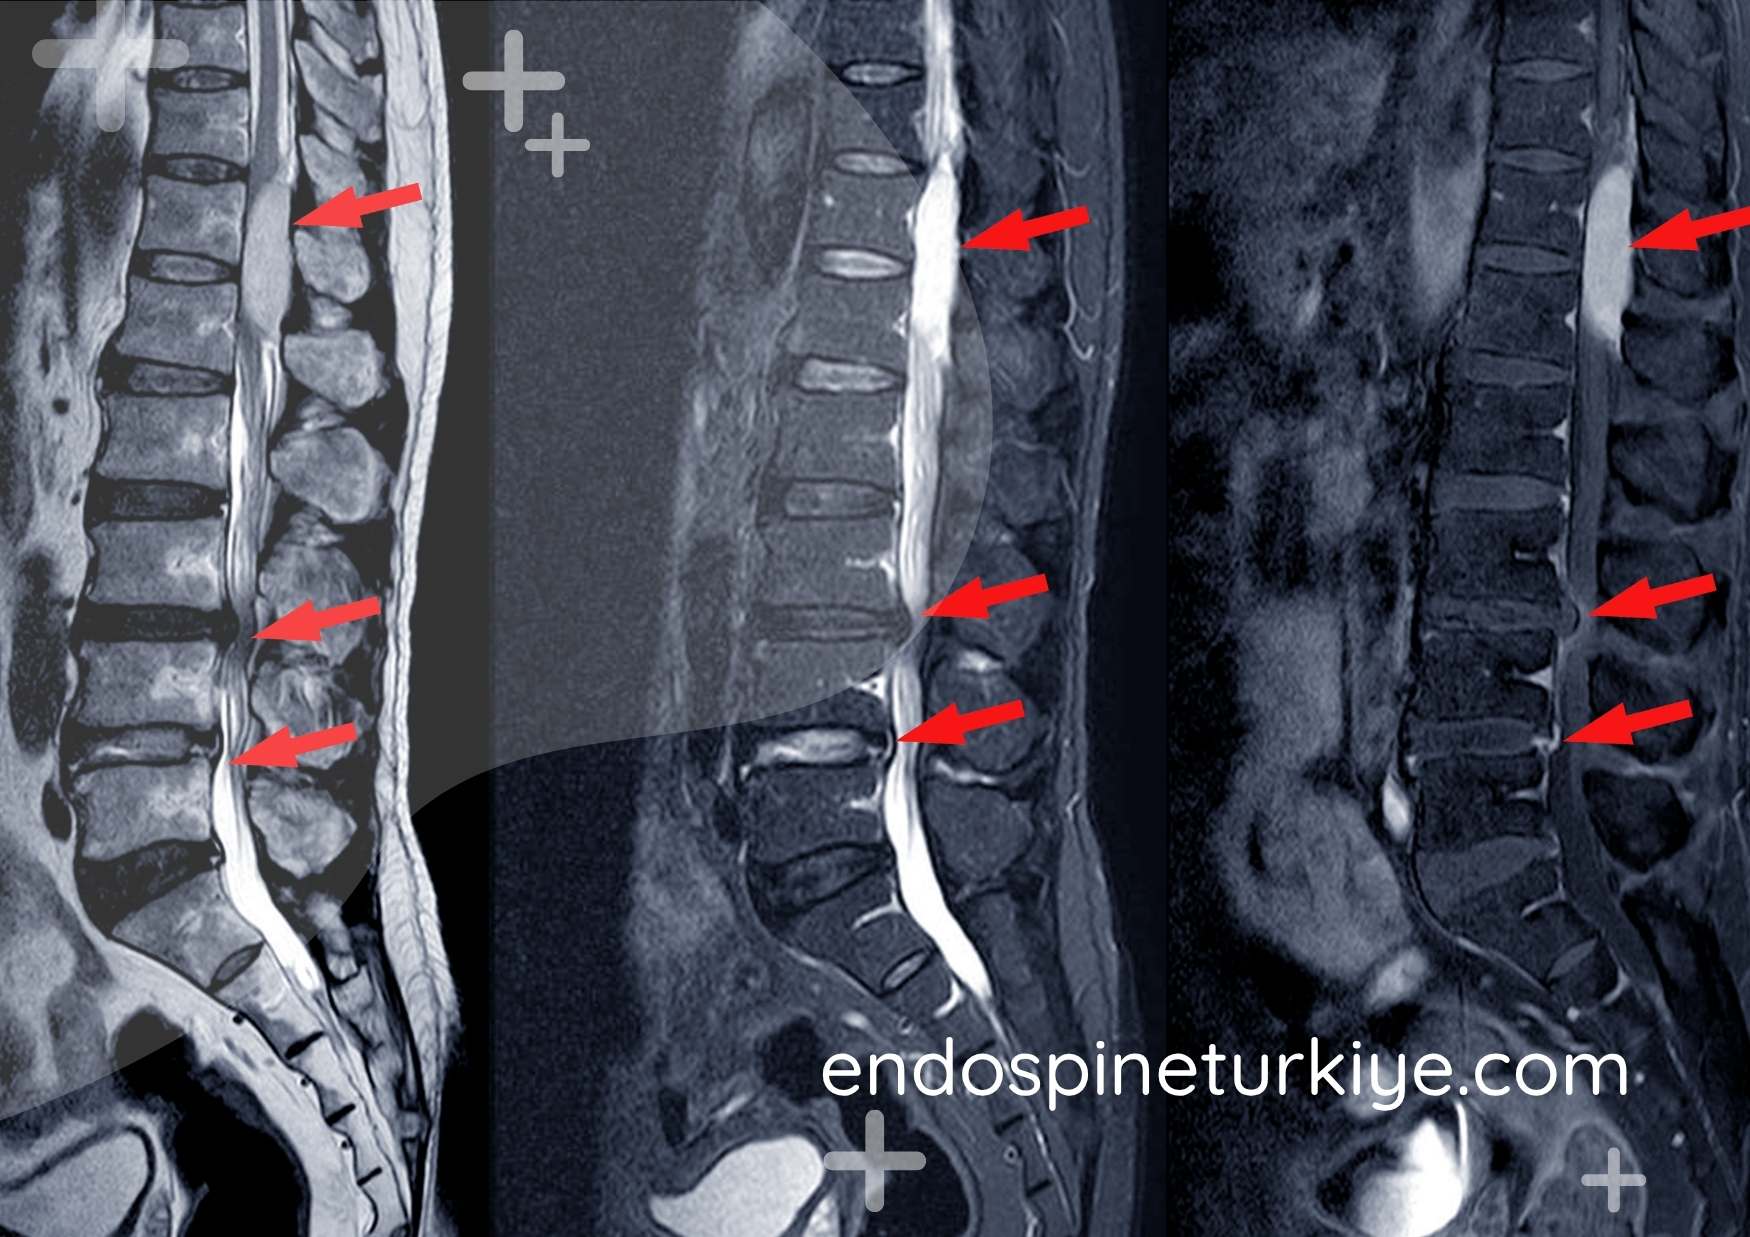

Dar Kanal Türleri

Merkezi Stenoz

Omurga kanalının ortasında meydana gelen daralma. En yaygın karşılaşılan formdur.

Lateral Reses Stenoz

Sinir kökünün geçiş bölgesinde yanal yönde oluşan daralma.

Foraminal Stenoz

Sinir kökü çıkış kanalının daralması. Üst ya da alt ekstremitelere yayılan ağrı.